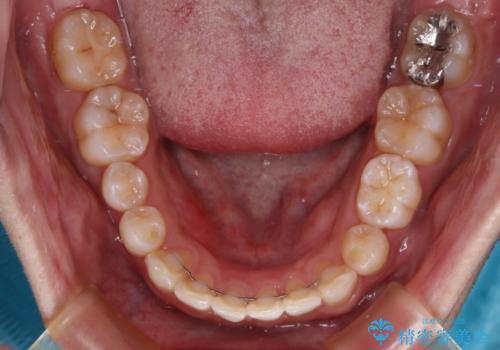

右上と左下は永久歯が欠如しており、大きさの大きく異なる乳歯が残存していたため、奥歯の咬み合わせを構築するために苦労しました。

元々隙間の空いていた上顎の正中は、後戻りのリスクが高いため、下顎前歯同様ワイヤー固定を行いました。